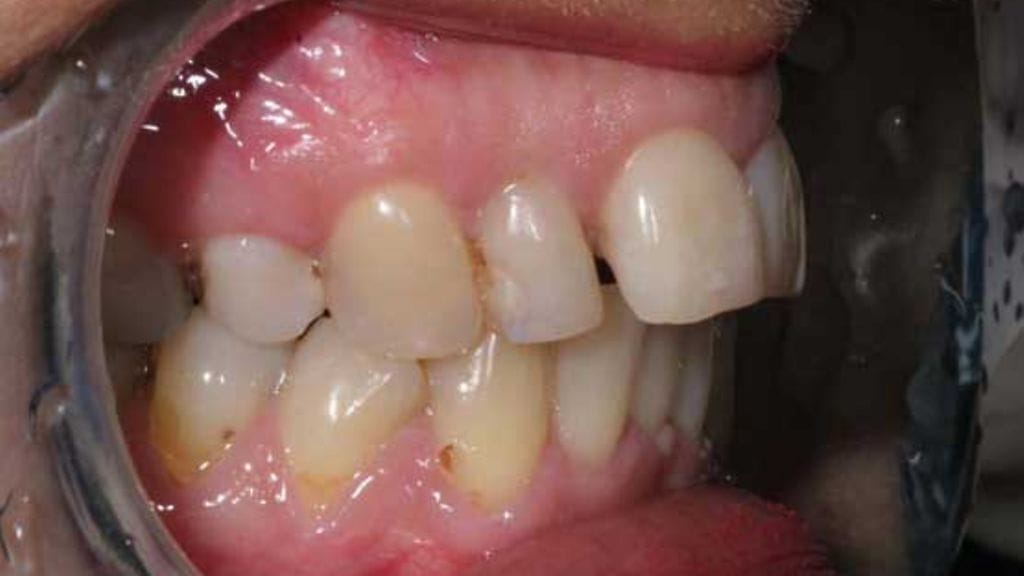

Hampaiden ulkonäköä pystytään tänä päivänä kohentamaan monin konstein. Katso kuvagalleriasta hämmästyttävät muutokset toimenpiteiden myötä!